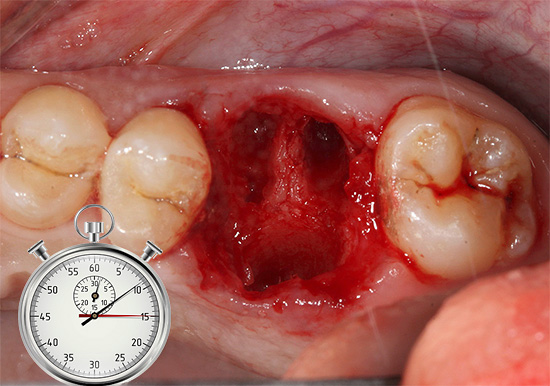

Após a extração do dente, muitas pessoas começam a se preocupar com outra pergunta - por quanto tempo o buraco e a gengiva lesionada curam? Isso se deve ao fato de que, algumas vezes após o procedimento, as gengivas começam a ser muito perturbadoras, geralmente o sangramento do orifício e a dor se estendem por vários dias.

Imediatamente após a extração do dente e o preenchimento do buraco com um coágulo sanguíneo, os mecanismos de sua cura começam a prever com precisão por quanto tempo as gengivas cicatrizam é bastante problemático, uma vez que esse processo é amplamente individual por natureza e é influenciado por vários fatores. No entanto, com as informações necessárias, você pode não apenas acelerar a restauração das gengivas e ossos no orifício do dente extraído, mas também tornar a fase de cicatrização relativamente confortável e rápida.

Depois que o cirurgião dentário extrai o dente do buraco, começa o processo de cicatrização da ferida pela chamada intenção secundária. Isso significa que o ligamento circular ao redor do dente se contrai e as bordas das gengivas se juntam. A formação de um coágulo sanguíneo no poço tem um efeito muito benéfico no processo de cicatrização de uma ferida após a extração do dente - esse coágulo desempenha um papel importante como um tipo de proteção contra possíveis infecções. Consequentemente, em nenhum caso você deve remover esse coágulo, por exemplo, lavando intensamente a boca ou, principalmente, mecanicamente - com um dedo ou um palito de dente.

O coágulo sanguíneo é substituído por tecido de granulação por vários dias e, em seguida, é formado tecido osteóide. Em outras palavras, com o tempo, um novo osso com uma gengiva formada acima dele se forma no lugar do dente extraído.